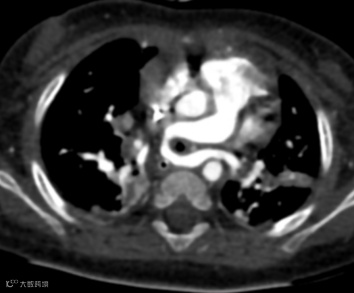

患儿,女,3月龄,出现喘息和喂养困难,肺动脉吊带,右位心。

轴位MIP图像显示心尖指向右侧,异常的左肺动脉(肺动脉吊带)起源于右肺动脉,穿过气管和食管之间,在气管远端分叉处导致管腔轻度狭窄,并压迫右主支气管使其近端狭窄,从而引起上呼吸道症状。